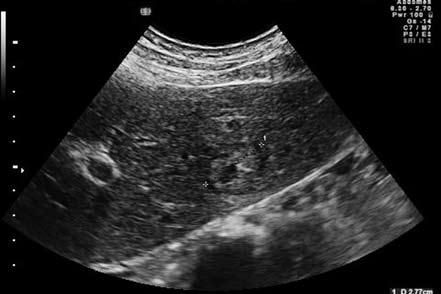

Рис. 62. Ультрасонограмма органов брюшной полости: метастаз рака кардиального отдела желудка в левой доле печени

Ультразвуковое исследование (УЗИ) при раке желудка проводится тремя способами: 1) трансабдоминальное исследование, при котором можно увидеть метастазы в печени, распространение опухоли на поджелудочную железу, увеличенные регионарные лимфатические узлы, да и саму опухоль, если она достаточно больших размеров и доступна визуализации; 2) полипозиционное полипроекционное исследование желудка после заполнения его дегазированной жидкостью для улучшения визуализации стенок органа. При этом можно увидеть саму опухоль и оценить не только ее размеры, но и распространенность; 3) исследование стенки желудка внутриполостным ультразвуковым датчиком, при котором можно оценить глубину инвазии стенки желудка опухолью, состояние перигастральных лимфатических узлов. В целом диагностическая чувствительность ультрасонографического метода колеблется от 70 до 80 %, что позволяет повысить точность дооперационной диагностики, правильно определить стадию опухолевого процесса. УЗИ гораздо более эффективно для выявления метастазов опухоли.

Такими признаками являются:

1) Регионарная лимфаденопатия. Отчетливо выявляется увеличение лимфатических узлов в парааортальной клетчатке, в зоне левой желудочной артерии, в парапанкреатической клетчатке по верхнему краю поджелудочной железы и по ходу селезеночной артерии, в воротах печени и селезенки.

2) Очаговые поражения паренхиматозных органов: печени, селезенки, почек, предстательной железы (рис. 62).

3) Наличие локального и тотального асцита.